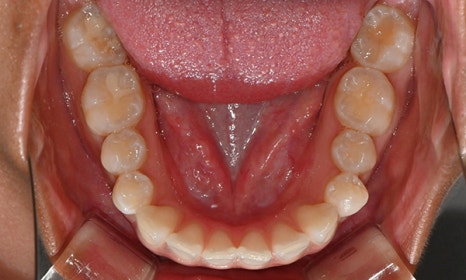

위아래 앞니 사이가 벌어져서 공간이 있었고, 앞니에 약간씩 배열이 틀어진 덧니가 있었습니다. 정면에서 보았을 때 윗니와 아래 앞니가 깊게 물려서 아래 앞니가 잘 보이지 않는 과개교합 양상을 보이고 있었습니다. 또한 왼쪽 아래 작은 어금니가 90도 앞으로 돌아가서 좌측 치아 배열 및 교합이 좋지 않은 상태였습니다.

초진시 구내사진 (2025. 3.31)